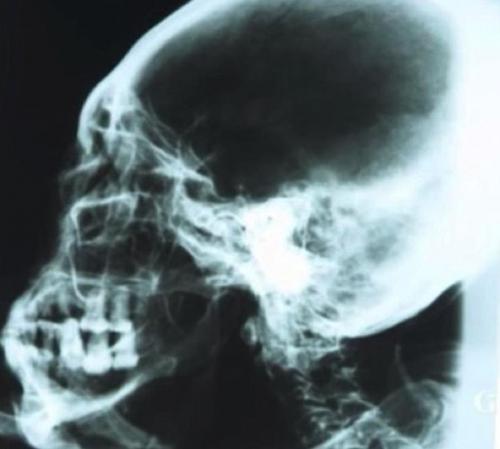

Пропорции тела у мумии в целом человеческие. В распрямленном состоянии ее рост составил бы 168 сантиметров. Очень странная голова с - удлиненным, вытянутым назад, черепом. Нос - крошечный, ушей - нет. Вместо них - едва заметные отверстия в черепе.

Мумия похожа на гипсовую скульптуру, посыпана каким-то белым порошком. Но, как показал рентген и компьютерная томография, это отнюдь не изваяние. Внутри - скелет, останки внутренних органов. Посредством радиоуглеродного анализа установлено, что тканям мумии 2300 - 2500 лет. Порошок, по мнению ученых, обладает бальзамирующими свойствами. Мумия им для сохранности обсыпана.